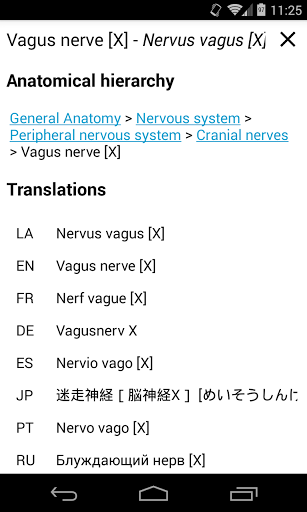

e-Anatomy memiliki lebih dari 26.000 gambar yang berisi serangkaian gambar dalam tampilan aksial, koronal, dan sagital serta radiografi, angiografi, gambar diseksi, bagan anatomi, dan ilustrasi. Semua gambar medis diberi label dengan cermat, lebih dari 967.000 label tersedia dalam 12 bahasa termasuk Terminologia Anatomica Latin.

- Ganti bahasa dengan satu sentuhan tombol